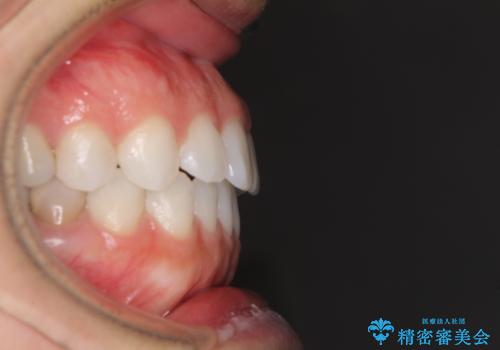

反対咬合を治したい インビザラインによる矯正治療

- 上下の前歯の反対咬合を気にして来院された患者様です。

インビザラインを用い、下顎はIPR(歯と歯の間を削る)と歯列全体を後方に移動させ、上顎は前歯を持ち上げることで、反対咬合を改善していくこととしました。